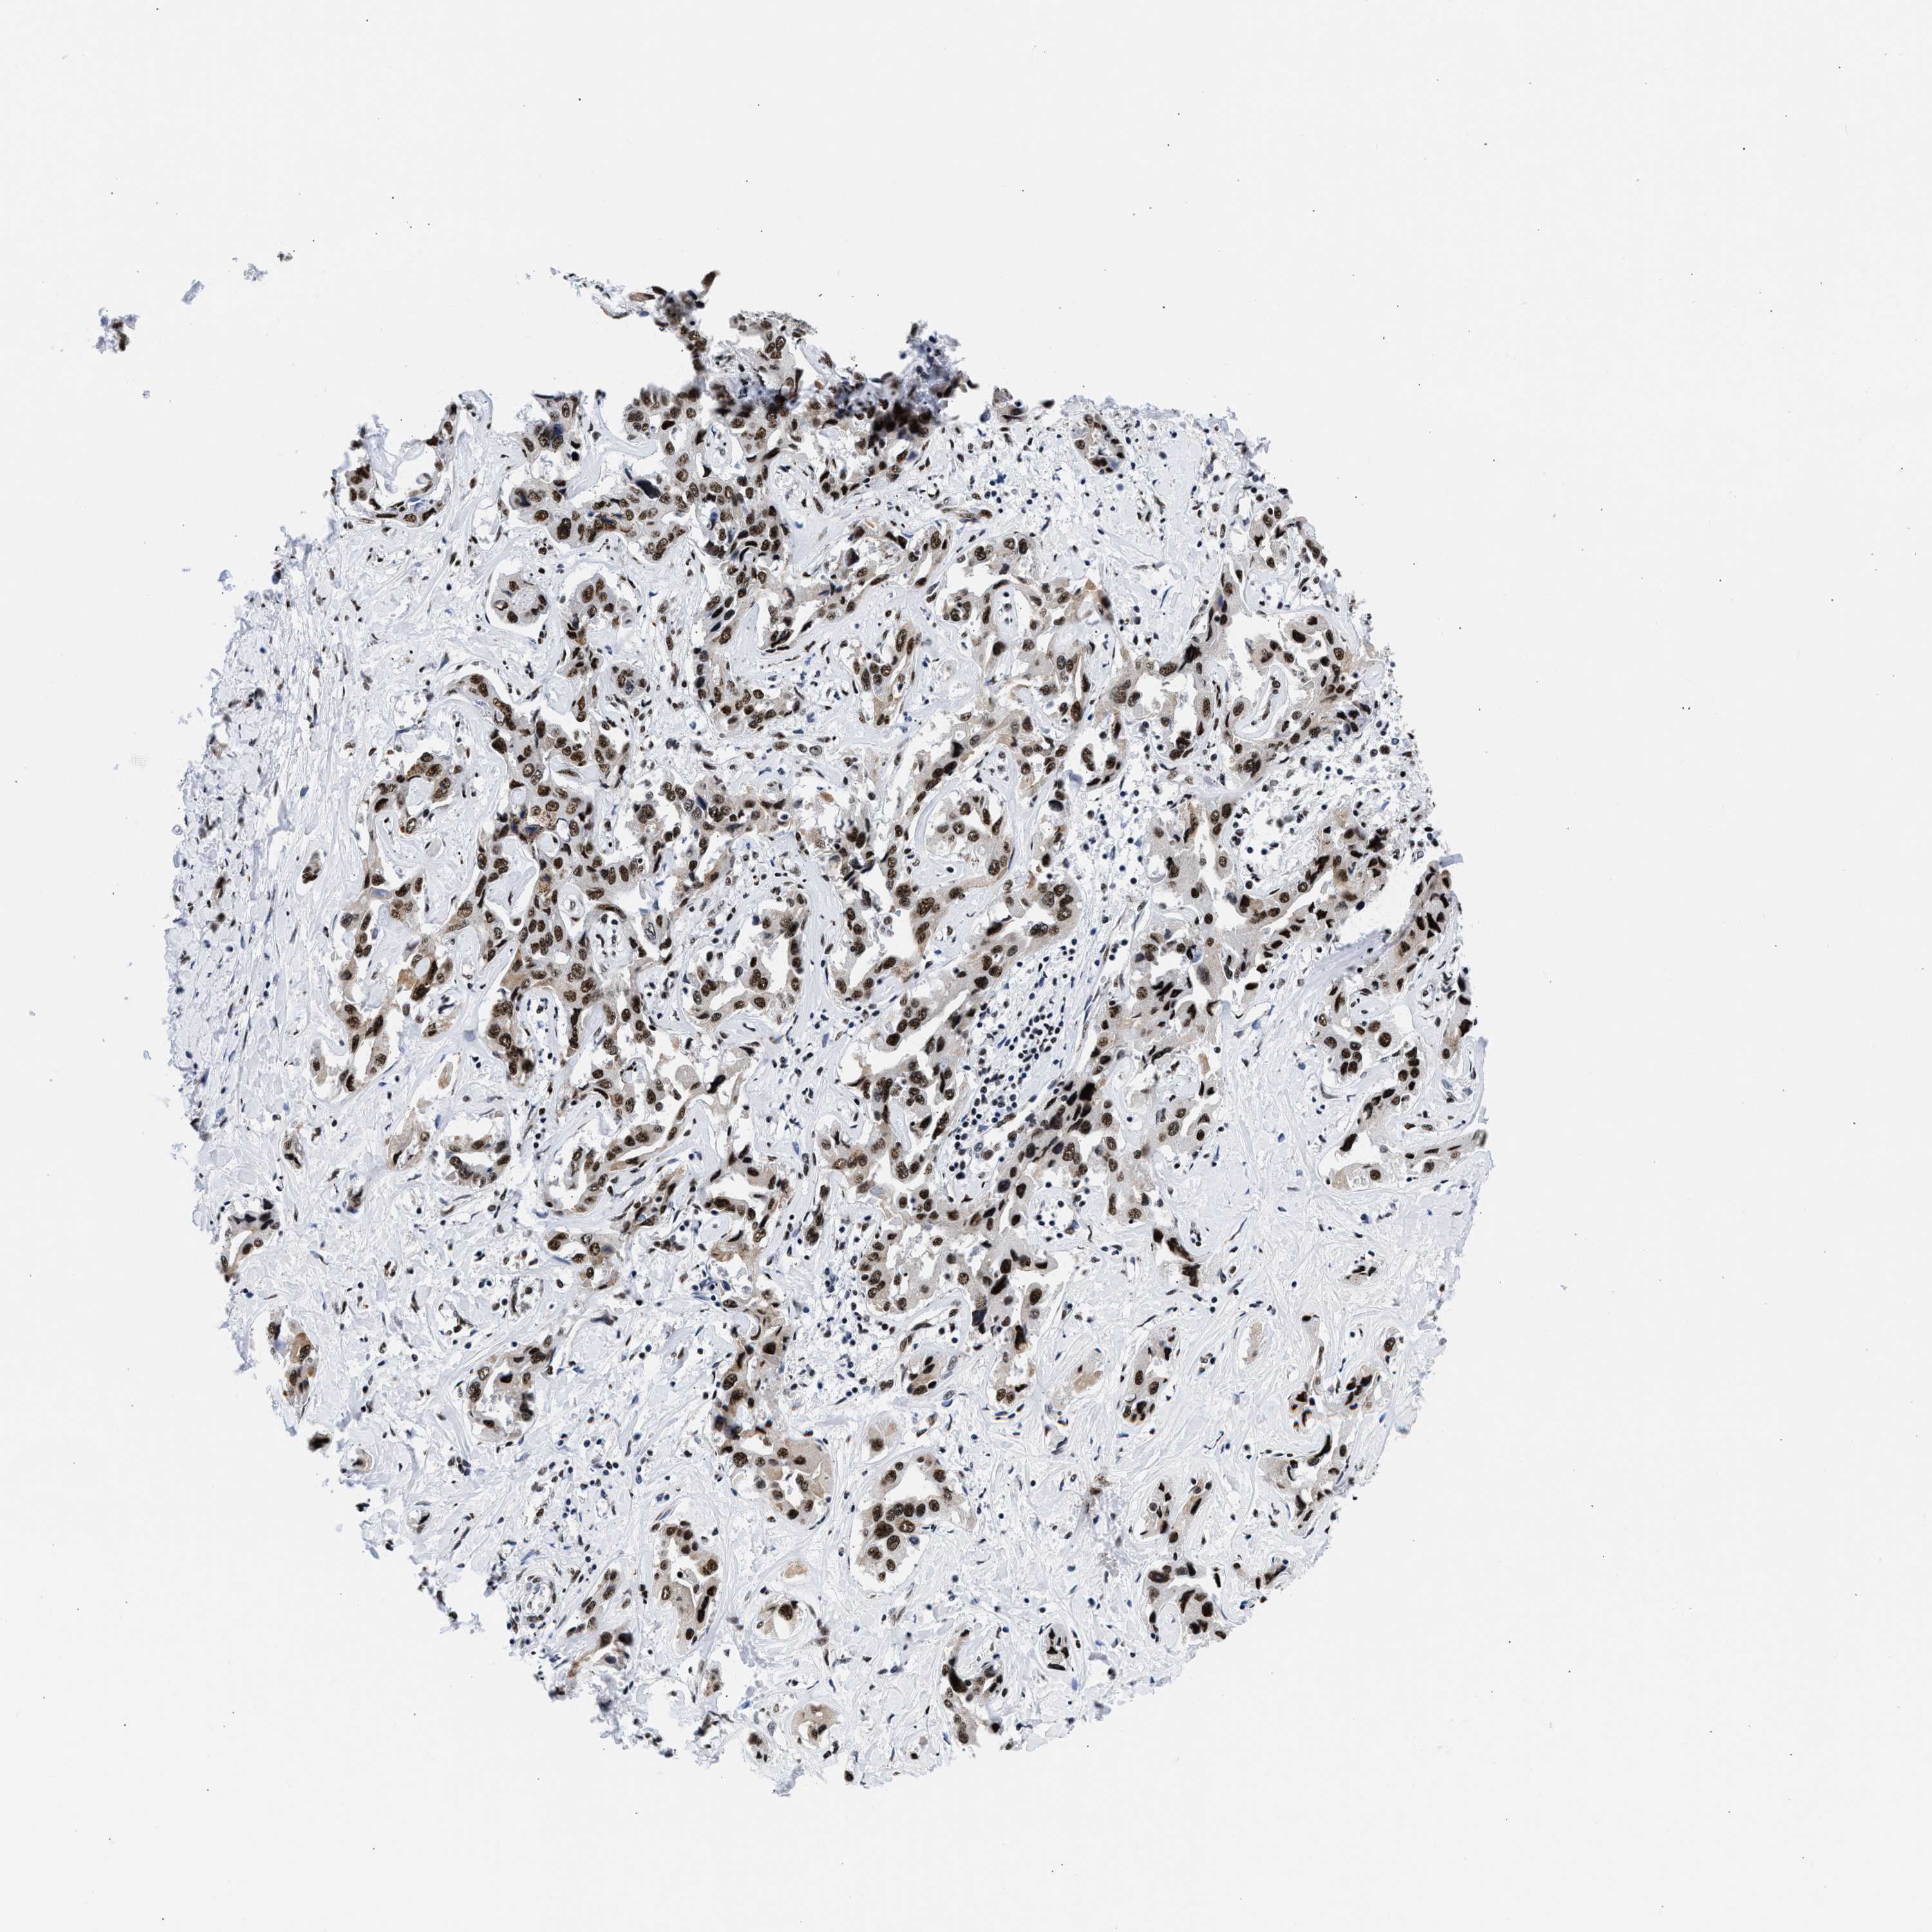

LIVER CANCER - Protein expressioni

A mouse-over function shows sample information and annotation data. Click on an image to view it in a full screen mode. Samples can be filtered based on level of antibody staining by selecting one or several of the following categories: high, medium, low and not detected. The assay and annotation is described here.

Note that samples used for immunohistochemistry by the Human Protein Atlas do not correspond to samples in the TCGA dataset.

Antibody stainingi

Antibody staining in the annotated cell types in the current human tissue is reported as not detected, low, medium, or high, based on conventional immunohistochemistry profiling in selected tissues. This score is based on the combination of the staining intensity and fraction of stained cells.

Each image is clickable and will lead to virtual microscopy that enables deeper exploration of all samples and also displays staining intensity scores, fraction scores and subcellular localization as well as patient and tissue information for each sample.

Antibody HPA018403

Staining

High

Medium

Low

Not detected

Intensity

Strong

Moderate

Weak

Negative

Quantity

>75%

75%-25%

<25%

None

Location

Nuclear

Cytoplasmic/membranous

Cytoplasmic/membranous,nuclear

Cholangiocarcinoma

Carcinoma, Hepatocellular, NOS